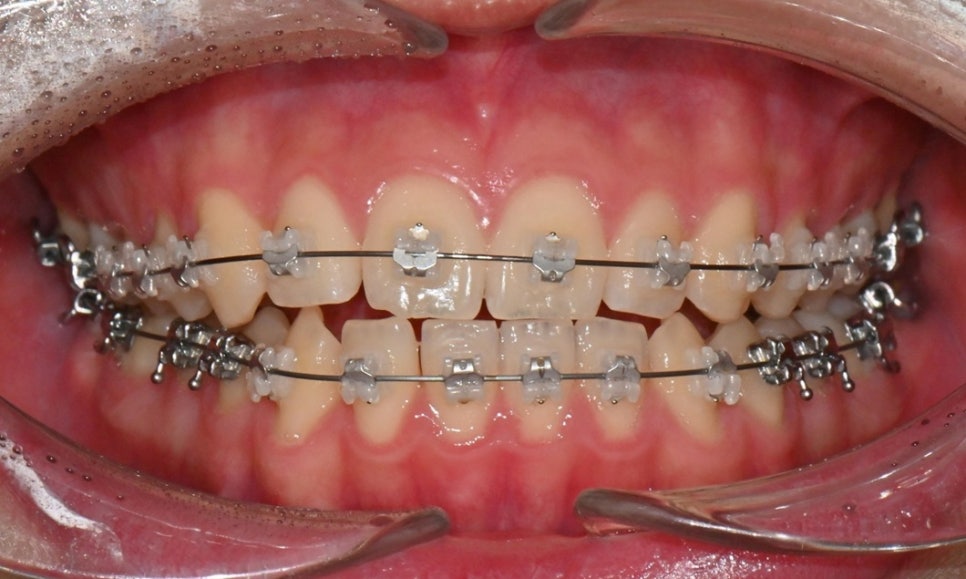

치료 시작 7개월 후 - 연세정원치과

치료 시작 7개월 후 사진으로, 치아 배열 후 아래 우측에 미니스크류를 식립하여 치아 중심선을 개선하는 중으로, 교합과 치아 중심선이 많이 개선된 것을 확인할 수 있습니다.